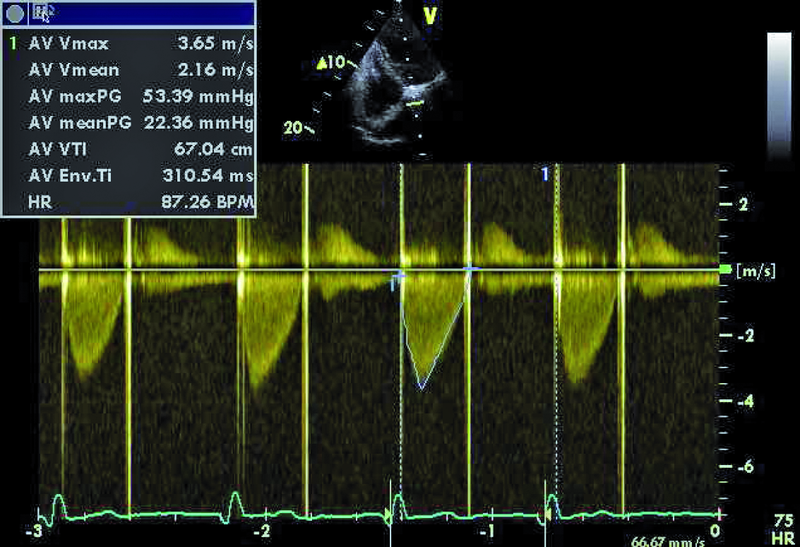

3. Podwyższone gradienty przepływu przez sztuczną zastawkę aortalną (ryc. 3).